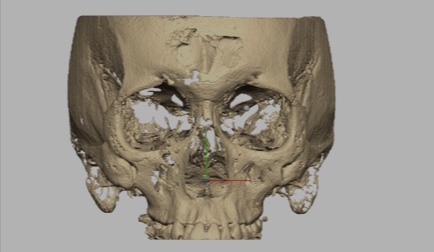

R2GATE® facial analysis: unique function that defines mid-facial plan, skeletal asymmetries, & esthetic problems

CBCT Reorientation

- Successful surgery requires accurate preoperative diagnosis & precise surgical planning

- CBCT analysis errors caused by slight patient movement can have significant impact on final surgical outcome

- Reorientation function corrects any patient position error during CBCT scan to provide best data for precise diagnosis